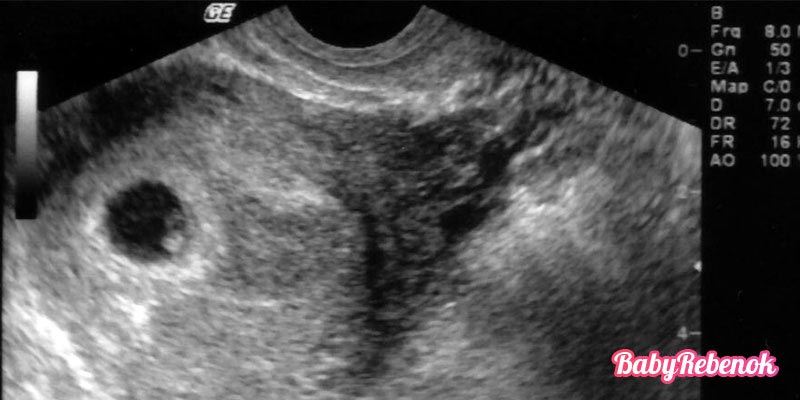

УЗИ на 6 неделе беременности

6 неделя беременности – это срок, когда при помощи аппарата УЗИ можно рассмотреть только плодное яйцо в матке и крохотного головастика — размер плода на 6 неделе беременности не более 5 мм внутри него. На данном этапе беременности у эмбриона выделяются только две основные части: голова и небольшое по сравнению с ней туловище, конечности же находятся в зачаточном состоянии.

Кроме того, именно на 6 неделе беременности при наличии хорошего ультразвукового аппарата можно увидеть первые сократительные движения сердечной мышцы эмбриона, которая на этом сроке представляет собой лишь пульсацию предположительно в области сердца, самого же органа еще не видно.

Фото плода — УЗИ на 6 неделе беременности